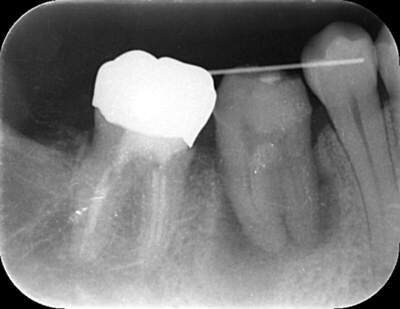

移植した歯

移植した歯のレントゲン写真

説明:

移植した歯の写真です。隣の歯とワイヤーで固定します。約3週間でワイヤーは外します。

3週間後

3週間後のレントゲン写真

移植後3週間経ったら根管治療を行います。根管治療後はレントゲン撮影をし、お薬がしっかり根の先まで充填できているか確認します。この後、土台をたてて、かぶせ物をかぶせて治療終了です。